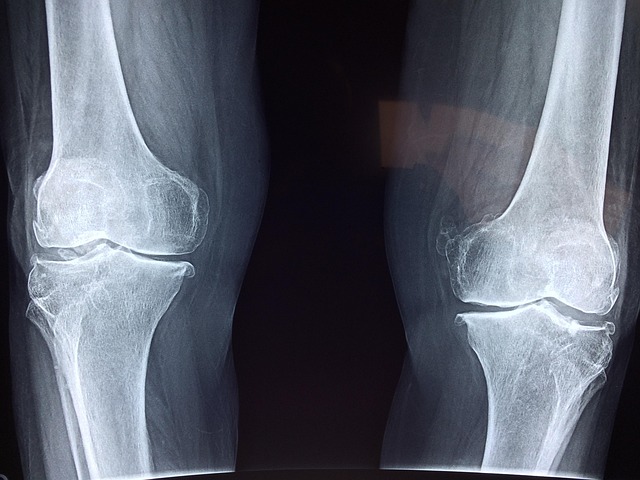

- 흉부 X-ray: 폐결절, 석회화, 음영 증가, 폐기종